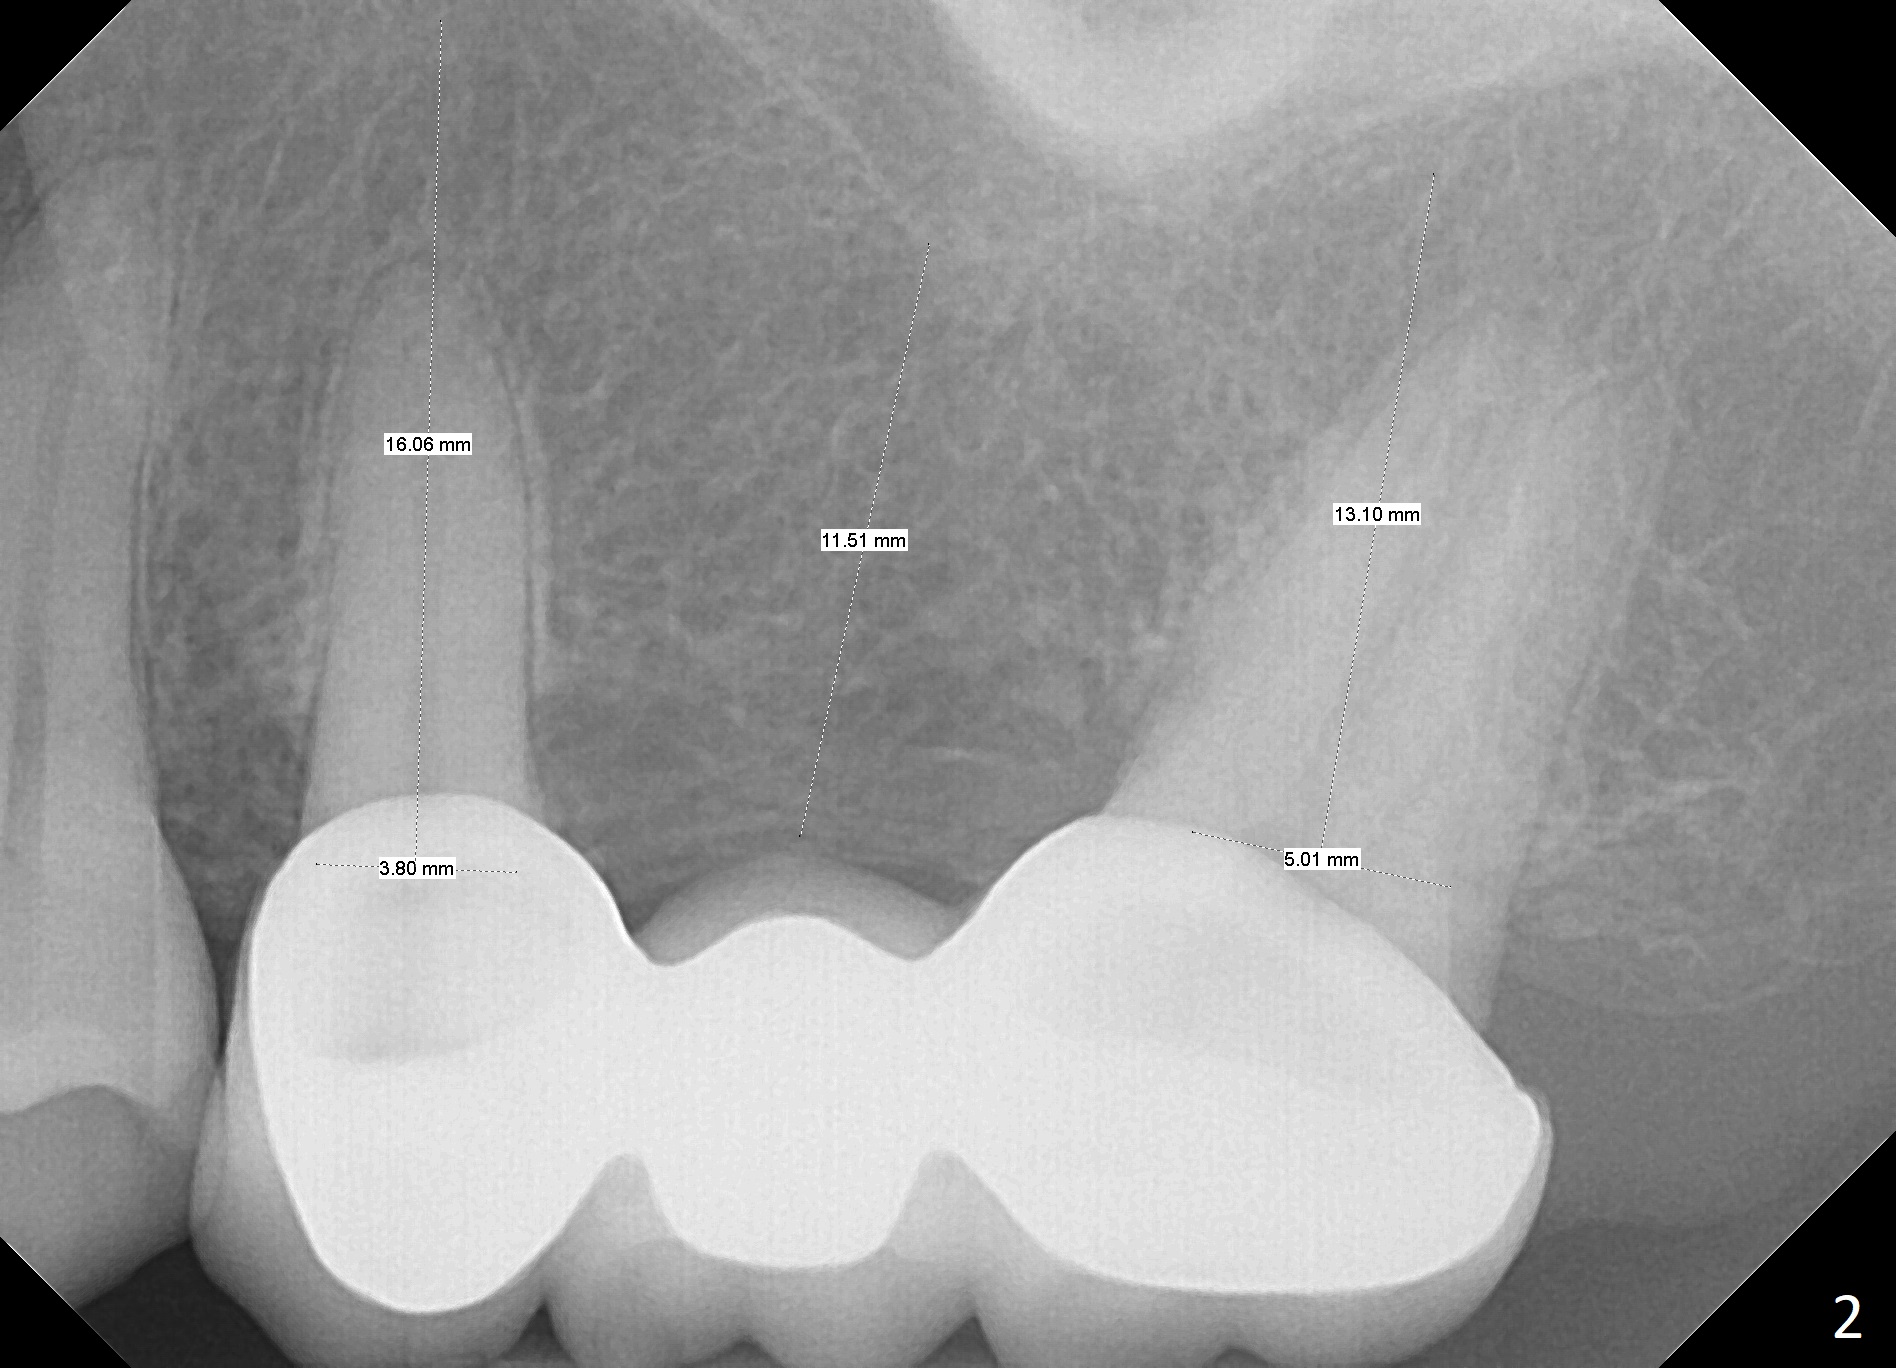

A 50-year-old woman has multiple restoration (Fig.1,2). There is discomfort with the upper left FPD, which will be removed (without local anesthesia initially) for exploration and SRP. Use a metal quadrant tray to take Alginate impression prior to FPD removal. If the abutments at #13 and 15 are to be extracted, an IS implant will be placed at the edentulous area. If the ridge is narrow and the bone is soft, use DIO bone expanders. If one or both of the abutments are non-salvageable, place UF immediate implant(s).